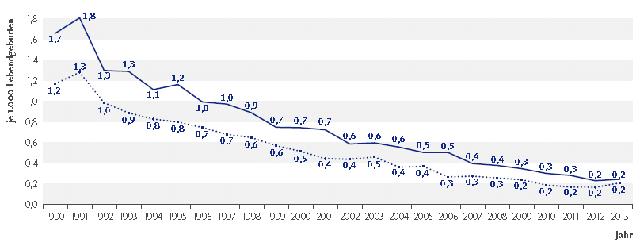

Plötzlicher Kindstod: Häufigkeit und betroffene Altersgruppen

Der plötzliche Kindstod, auch bekannt als Sudden Infant Death Syndrome (SIDS), ist ein seltenes Ereignis. Im Jahr 2020 waren in Deutschland insgesamt 84 Kinder davon betroffen. Die Anzahl der Todesfälle durch SIDS ist seit Jahren rückläufig.

Das Risiko des plötzlichen Kindstods ist am höchsten bei Säuglingen zwischen dem zweiten und vierten Lebensmonat. Ab dem sechsten Lebensmonat nimmt das Risiko deutlich ab, und bei Babys über einem Jahr tritt SIDS kaum noch auf.